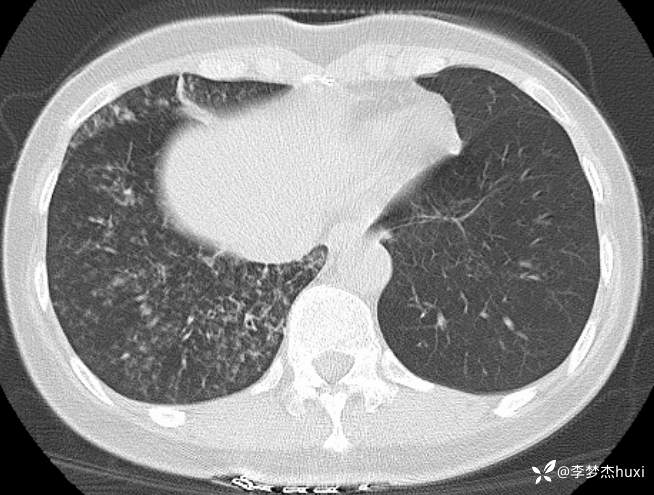

女性53岁,腮腺癌术后反复咳嗽、咳痰,胸部CT以树芽征为特点改变,最可能的是哪种疾病

【现病史及既往史】: 1.患者中年 女,患者于入院前5天无明显诱因出现咳嗽,咳痰,为黄绿色痰,量少,不易咳出,伴发热,最高体温不详,伴周身乏力,无胸痛,无呼吸困难,无恶心、呕吐,无腹痛、腹泻,无抽搐及意识障碍,院外未诊治,症状无好转,今患者及家属为进一步诊治前来我院就诊,门诊查胸部CT:右肺上叶占位性病变应考虑,右肺上叶空洞;右肺下叶占位?双肺炎症,支气管炎?右肺门淋巴结增大,双肺实性结节,纵隔结节,主动脉及冠状动脉钙化,右侧乳腺结节?建议结合超声,建议结合临床复查。门诊以“肺炎”收入院 。

2.既往高血压病史20余年,最高达180/?mmHg,目前口服“缬沙坦胶囊、硝苯地平控释片、酒石酸美托洛尔”等药物治疗,血压未监测;2008年因右侧腮腺腺样囊性癌于天津肿瘤医院行手术治疗,术后给予放化疗,2019年肿瘤原位复发,于北京大学口腔医院再次行手术治疗,2023-8发现肿瘤侵犯右耳道,目前口服仑伐替尼治疗约12个月;2023-11开始应用帕博利珠单抗注射液免疫治疗,患者右肺上叶占位,2024-7于沧州市中心医院行穿刺活检,病理:腺样囊性癌,2024-08于北京市某医院行“肺部射频消融术”;患者术后时常呛咳,否认“冠心病、糖尿病”病史,否认“肝炎”、“结核”等传染病史;否认外伤史,无输血史;否认食物、药物过敏史,预防接种史不详,系统回顾无特殊。。

【临床诊断】: 1.肺炎

2.肺恶性肿瘤 (腺样囊性癌)射频消融术后。